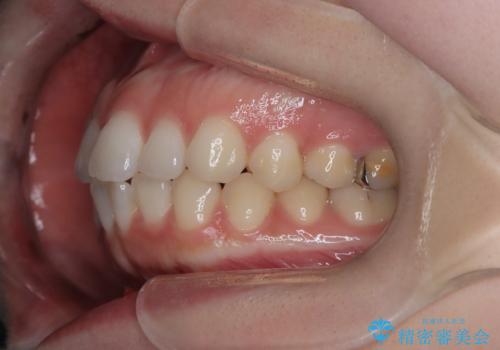

- 右上の八重歯と歯並びのデコボコを気にされて来院されました。精密な検査の結果、歯列のスペースがわずかに不足していることが判明。患者様の「抜歯を避けたい」というご希望を最大限に尊重し、アンカースクリュー(TAD)を用いて奥歯(臼歯部)全体を後方へ移動させることで、八重歯が並ぶスペースを確保する治療計画を立案しました。装置にはワイヤー矯正を使用し、確実で効率的な歯の移動を目指します。

今回のワイヤー矯正治療では、抜歯せずに歯を並べるスペースを作るため、特殊な小さなインプラントであるアンカースクリュー(TAD)を一時的に使用しました。このアンカースクリューを固定源として、奥歯(臼歯部)全体を後方へ遠心移動させました。従来の矯正では難しかったこの奥歯の移動を確実に行うことで、前歯の八重歯を適切な位置に並べるスペースを確保。治療の結果、抜歯することなく右上の八重歯と叢生が解消され、機能的にも審美的にも整った美しい歯並びを獲得していただけました。